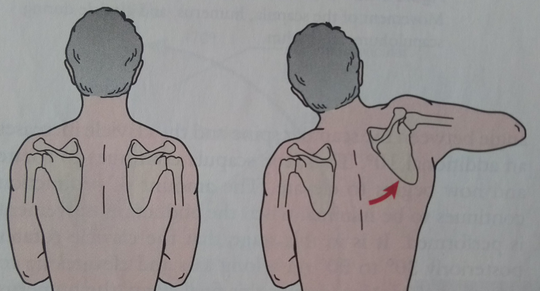

もし、肩関節が左右非対称にしか動かせなかった場合は、以下のことが考えられる。

患側の胸鎖関節が機能しない場合、肩関節外転は肩甲上腕関節が120度までの外転で限界となる。

肩甲上腕関節が機能しない場合、肩甲胸郭関節を十分に機能しても外転60度が限界である。

肩関節外転の際に、上腕の外旋が出来ない場合は全体の機能として可能な関節可動域は120度までであり、そのうちの60度は肩甲上腕関節60度、肩甲胸郭関節60度である。

上腕よりも肩甲骨が機能する場合が上図である。この状態がフローズン・ショルダー(凍結肩・五十肩)である。肩関節の外転に関して複数の筋の機能が調和して機能していないことが原因で、単独の筋の損傷だけでは説明がつかない。